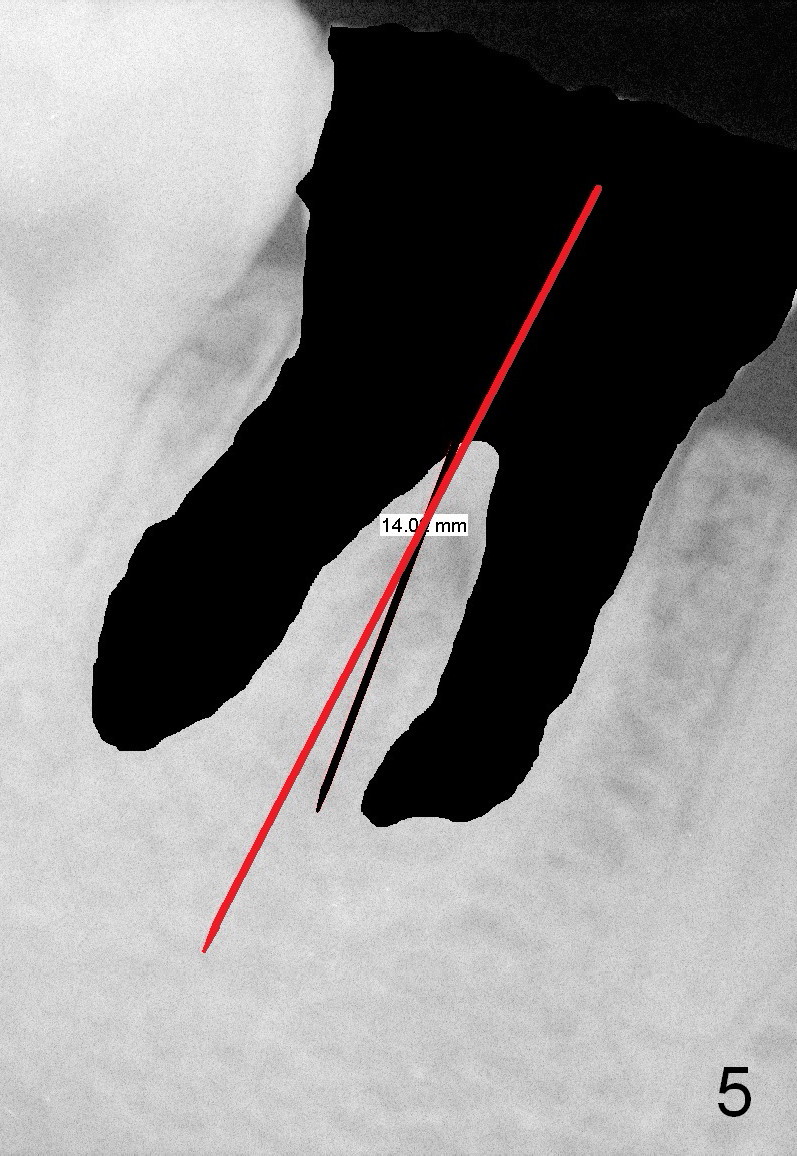

First of all, use a sharp small pilot drill (1.2, 1.5 or 2.0 mm) 3 mm shy of the extended length. For this case, the initial depth will be 14 mm from the gingival margin (Fig.3: red long arrow). If the drill is straight and in the middle of the septum (1st intraop PA), keep drilling for the next 3 mm. If the trajectory is off (Fig.4), withdraw the drill (Fig.5 black long arrow), find a new starting point, change the trajectory and finish osteotomy depth (red long arrow) if the new trajectory is deemed correct. Take more X-ray if necessary.